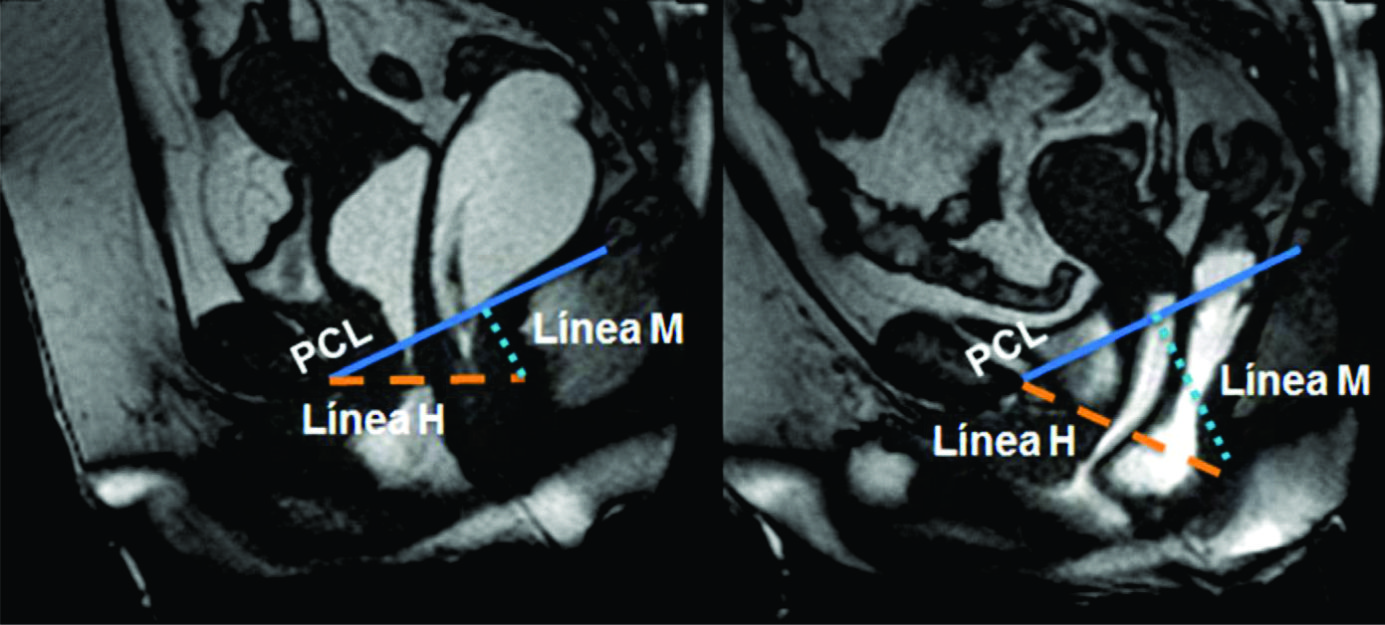

Figura 4

Línea H y línea M.Imágenes potenciadas en T2 de alta resolución en el plano sagital. Se observa el cambio en el valor que adopta la línea M y la línea H al comparar el reposo frente a la defecación. Según sus medidas en centímetros, se puede graduar en cuatro estadios diferentes.

La línea pubococcígea (PCL) se extiende desde el borde inferior del pubis a la última articulación coccígea y representa el nivel de piso pélvico, constituyendo la línea de referencia a partir de la cual se miden los prolapsos, tanto en reposo como en Valsalva.

La línea H se traza desde el borde inferior del pubis hasta la pared posterior del recto a la altura de la unión ano rectal, representando el diámetro anteroposterior del hiato urogenital, con un valor normal menor a 6 cm (Ver figuras 4).

La línea M es perpendicular a la PCL a nivel del sector más posterior de la línea H y representa el descenso del hiato del elevador, con un valor normal menor a 2 cm. El ángulo ano rectal es el ángulo entre el eje central del canal anal y la pared posterior del recto, con un valor normal entre 108º y 127º y una variación de hasta 15º en Valsalva.

Además se debe valorar la relajación del piso pélvico, a través del valor que adquiere tanto la línea H (apertura del hiato urogenital) como la línea M (descenso del piso pélvico) durante las maniobras dinámicas (Ver tabla 4) (7).